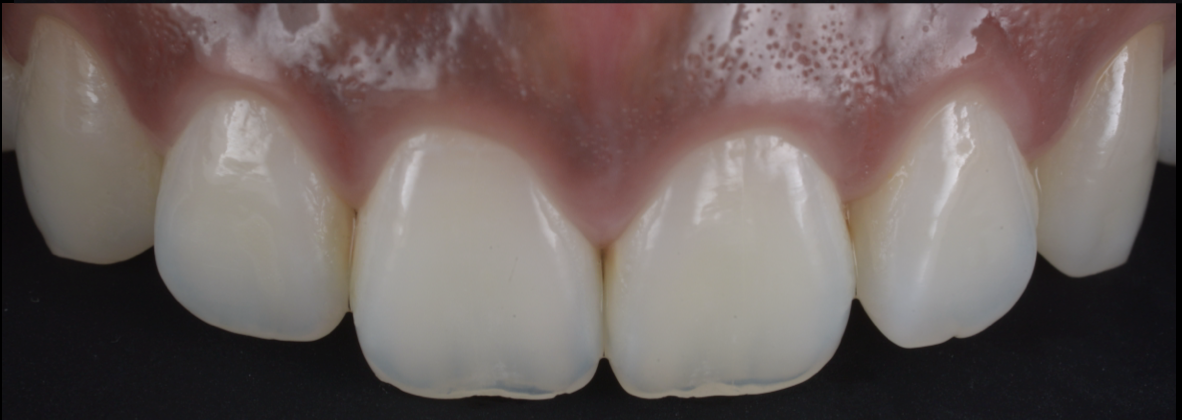

上唇の腫脹を認め、CT検査にて根尖部に嚢胞様透過像を認めた。左上の前歯が不自然に大きく噛み合わせが強くなっていたことがフレアアップの一因と考える。精密根管治療を行い、感染経路を遮断したのち歯根端切除術にて嚢胞を摘出した。

治療後

歯の保存、嚢胞の摘出、審美的改善